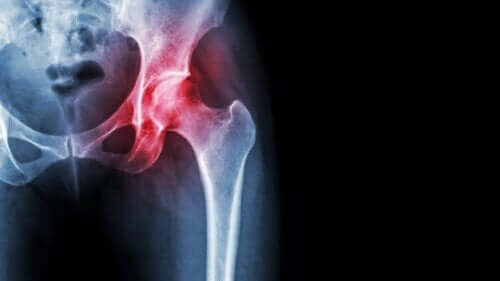

Jałowa martwica głowy kości udowej

Jałowa martwica to obumieranie tkanki kostnej. Dlaczego się rozwija? W jaki sposób odbija się nażyciu pacjentów? Czytając dzisiejszy artykuł poznasz najważniejsze informacje na ten temat.

Jałowa martwica, podobnie jak każda inna martwica, pojawia się w wyniku braku dostarczania krwi do tkanek. W tym przypadku dotyka kości, co prowadzi do rozwoju poważnych konsekwencji.